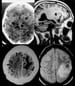

Neuroimaging in neurocysticercosis. CT scans showing different phases of neurocysticercosis. Top left: CT scan showing many calcifications and active cysts with scolices in both hemispheres. Top right: T1-weighted MRI showing 2 active cysts with the scolex in their interior (vesicular phase). Bottom left: Postcontrast CT scan showing a ring-enhancing cyst (colloidal phase) on left. Bottom right: Proton density-weighted MRI showing a thick capsule with adjacent scolex and perilesional edema (colloidal phase).